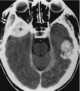

Temporal lobe hematoma

Intracerebral hemorrhage (ICH), also known as cerebral bleed and intraparenchymal bleed, is a sudden bleeding into the tissues of the brain, into its ventricles, or into both. It is one kind of bleeding within the skull and is one kind of stroke.Symptoms can include headache, one-sided weakness, vomiting, seizures, decreased level of consciousness, and neck stiffness. [Source: Wikipedia ]